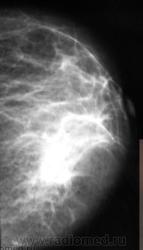

Сегодня проводились проф.осмотры. Наиболее интересные случаи я решил показать коллегам. Жалоб пациентки не предъявляли.

Сложно оринетироваться без маркировок, более плотный участок где он в косой проекции? Сохраняется, раходится на составляющие, Представлена одна железа, обе?

Иногда, в возможностях маммографии при наличии таких участков, по всей видимости, можно усомниться.

Валентин Львович, вы абсолютно правы, в таких ситуациях необходимо дополнять стандартное маммографическое исследование  проекциями под другими углами  и если такая картина сохраняется, делать УЗИ, направлять к онкологу.